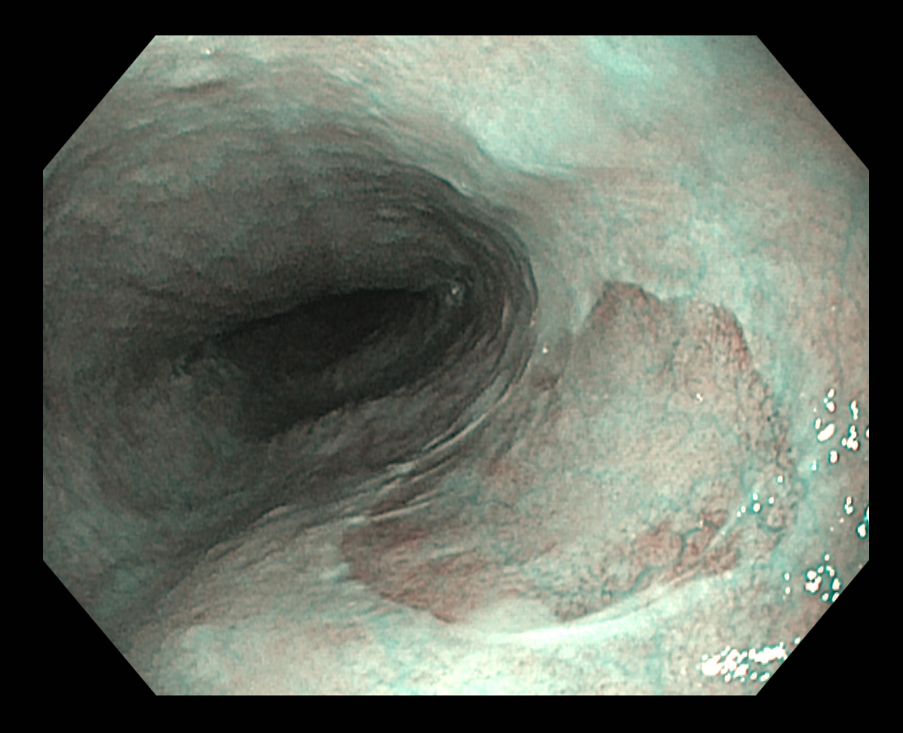

식도 상부에서 전형적으로 발견되는 위점막과 닮은 구별되는 영역. 일반 인구에서 유병률은 autopsy에서 약 5%인 반면 위내시경 연구에서는 상부위장관내시경을 시행하는 환자에서 0.4~11%. 내시경 연구에서 유병률이 더 낮은 이유는 inlet patches가 식도 상부에 위치하고 있기 때문인 것 같습니다. 가장 일반적으로는 UES 아래 식도 3 cm 부위에서 발견되며 이 부위는 일반적인 상부위장관내시경 동안에 잘 보여지는 곳은 아닙니다. Inlet patches는 모든 연령에서 기술되었지만 가장 일반적으로 발견되는 나이는 50대 중반입니다.